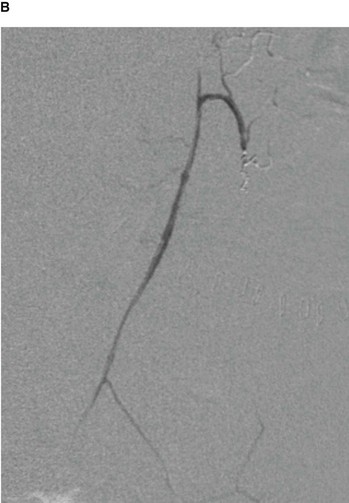

An ideal place to situate the transplant kidney is in the left or the right iliac fossa (Fig. 4.146). A curvilinear incision is made paralleling the iliac crest and pubic symphysis. The external oblique muscle, internal oblique muscle, transverse abdominis muscle, and transversalis fascia are divided. The surgeon identifies the parietal peritoneum but does not enter the peritoneal cavity. The parietal peritoneum is medially retracted to reveal the external iliac artery, external iliac vein, and the bladder. In some instances the internal iliac artery of the recipient is mobilized and anastomosed directly as an end-to-end procedure onto the renal artery of the donor kidney. Similarly the internal iliac vein is anastomosed to the donor vein. In the presence of a small aortic cuff of tissue the donor artery is anastomosed to the recipient external iliac artery and similarly for the venous anastomosis. The ureter is easily tunneled obliquely through the bladder wall with a straightforward anastomosis.

image image

Fig. 4.146 Kidney transplant. A. This image demonstrates an MR angiogram of the bifurcation of the aorta. Attaching to the left external iliac artery is the donor artery for a kidney that has been transplanted into the left iliac fossa. B. Abdominal computed tomogram, in the axial plane, showing the transplanted kidney in the left iliac fossa.

The left and right iliac fossae are ideal locations for the transplant kidney, because a new space can be created without compromise to other structures. The great advantage of this procedure is the proximity to the anterior abdominal wall, which permits easy ultrasound visualization of the kidney and permits Doppler vascular assessment. Furthermore, in this position biopsies are easily obtained. The extraperitoneal approach enables patients to make a swift recovery.